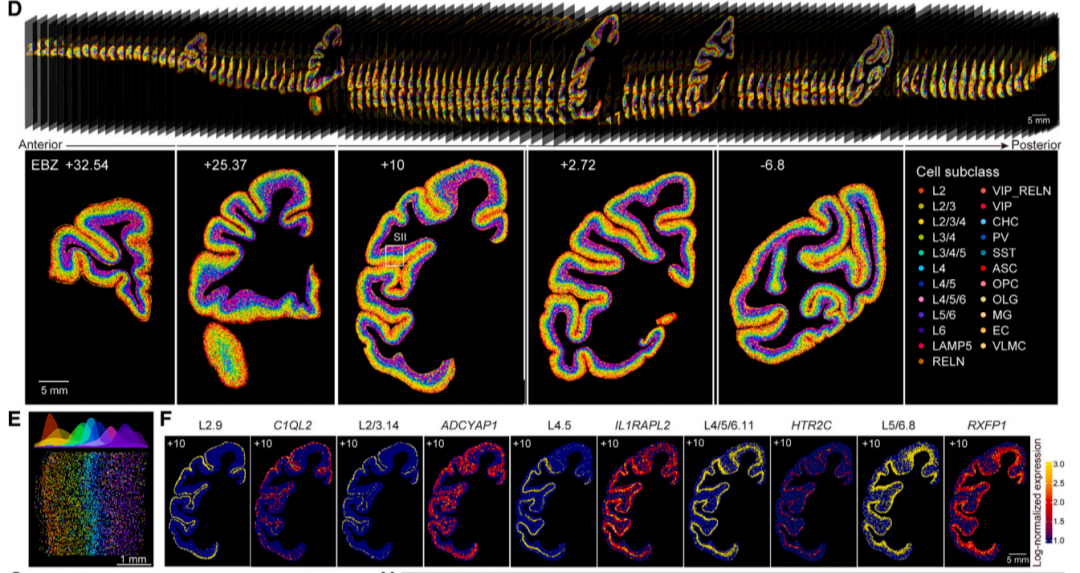

研究团队基于华大自主研发的时空组学技术Stereo-seq与高通量单细胞核转录组测序技术DNBelab C4 snRNA-seq,成功绘制了全球首个食蟹猴大脑全皮层的三维单细胞图谱,并且绘制了细胞类型分类树,揭示了细胞类型组成和灵长类脑区层级结构之间的关系。

猕猴大脑皮层细胞类型空间分布图谱

猕猴是演化上最接近人类的模式动物,其大脑皮层组织在很多方面与人类相似。猕猴脑细胞图谱的绘制,将帮助科学家更好地认识脑疾病,为未来人脑功能、脑疾病、脑机接口等脑科学领域研究的基础认知提供基础参考资源,大幅加快脑科学研究进程。